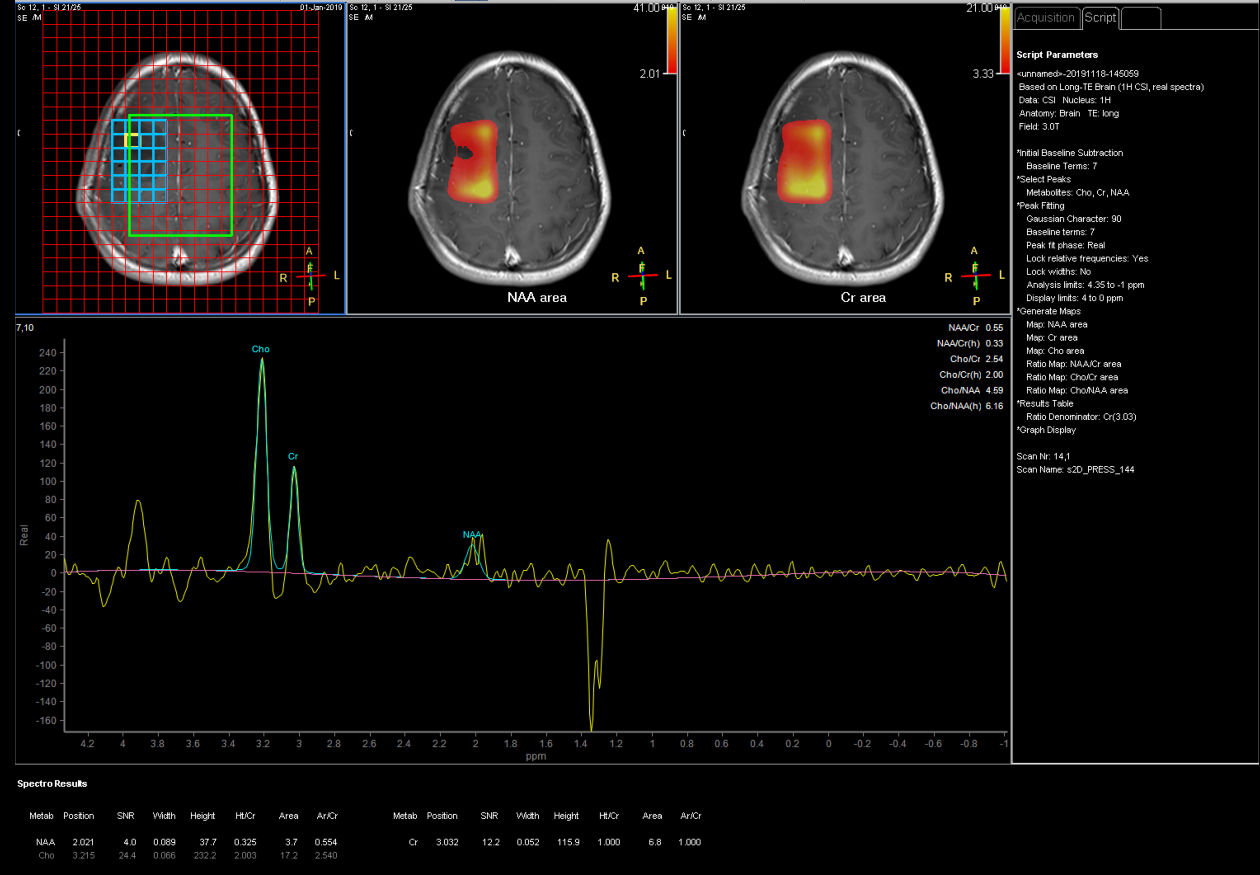

Spectroscopy

Patient with a brain lesion. ExamCard includes MultiVane XD for motion-free imaging in short scan time, Compressed SENSE to shorten exam time, SWIp to enhance contrast for deoxygenated (venous) blood or calcium deposits, a high resolution 3D FLAIR sequence enabling reformats in any plane without loss of resolution, diffusion to achieve high contrast between background and lesions, pCASL to visualize brain perfusion and functional physiology in a non-contrast manner, dynamic multi-slice T2* perfusion for quantitative analysis, and spectroscopy for a non-invasive measurement of biochemical changes in the brain.